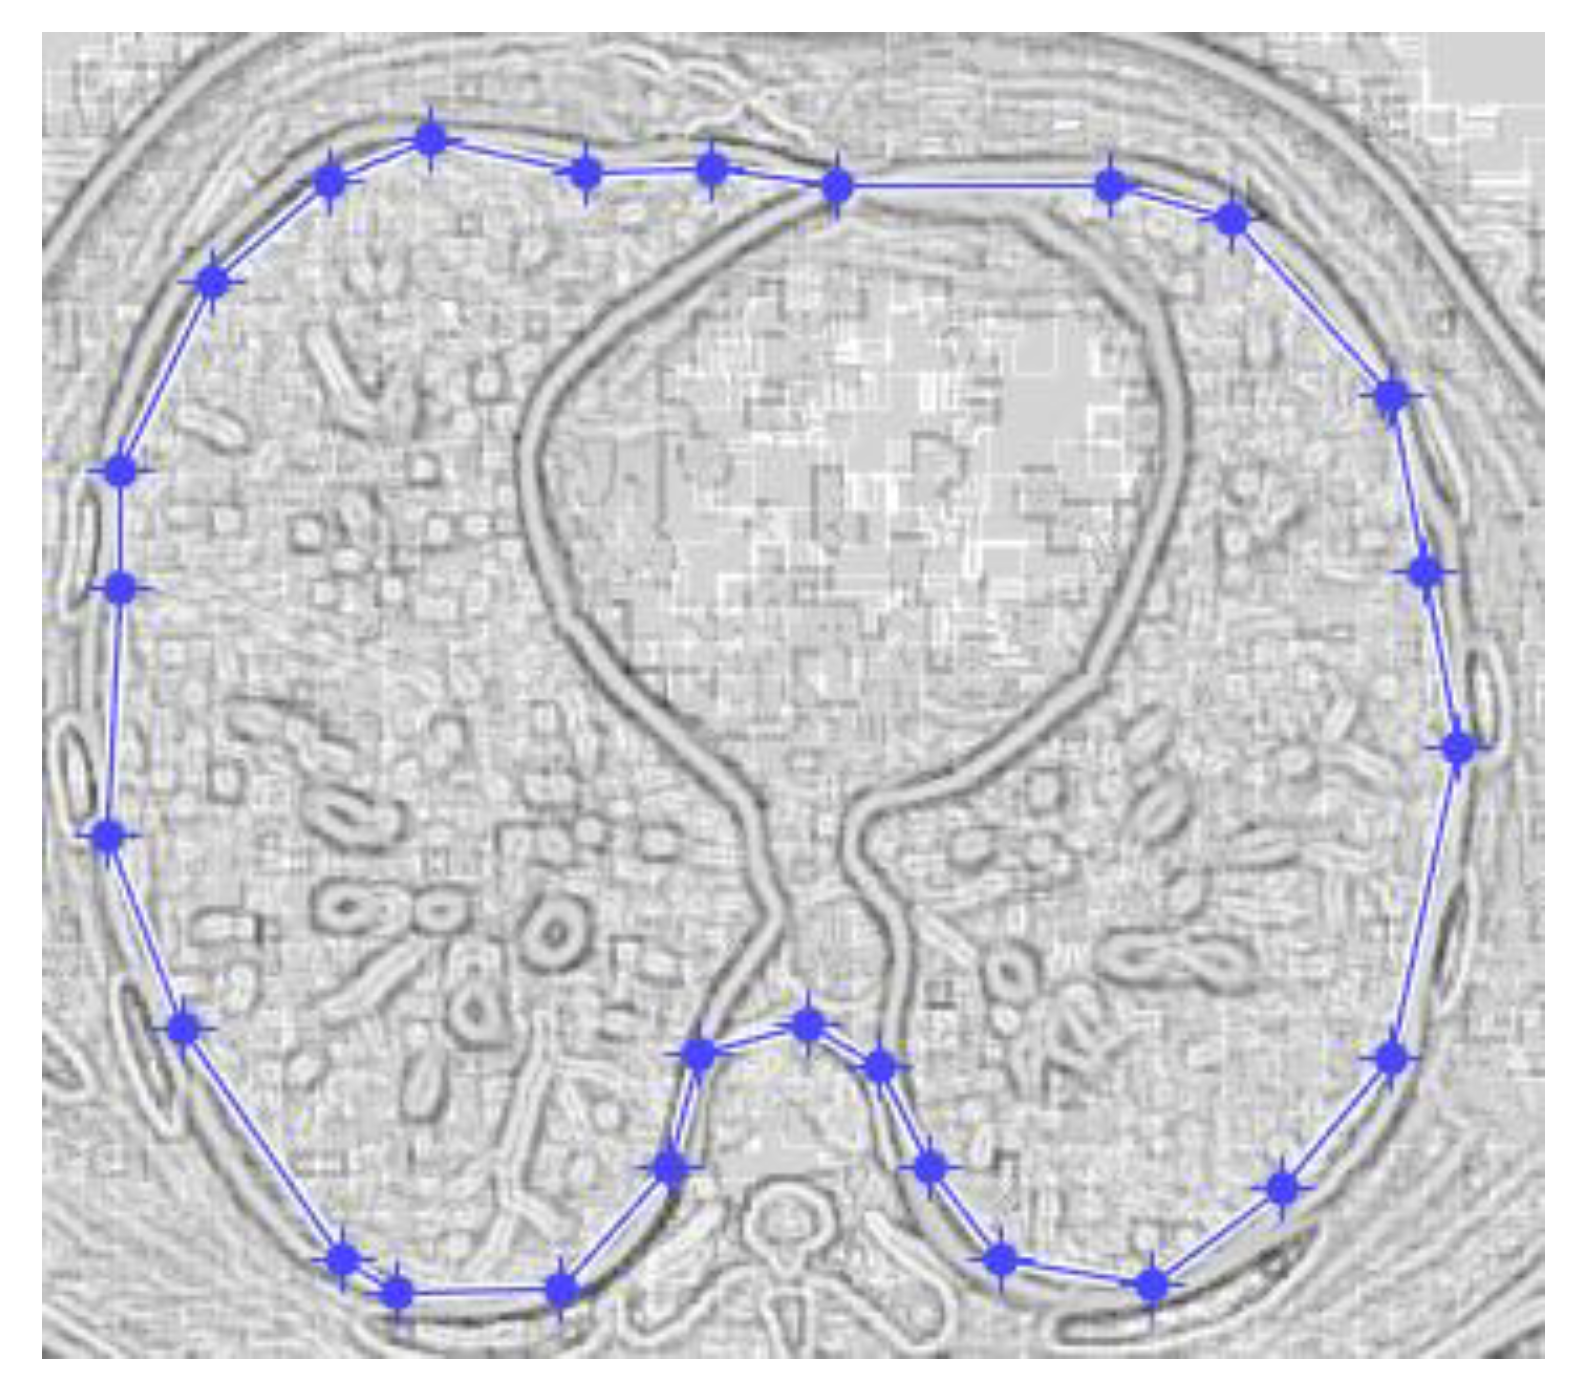

Figure 17 and Figure 18 show the original non-COVID-19 CT pulmonary picture, respectively, and the defined mask for the non-COVID-19 CT pulmonary picture, framed in a blue border, Figure 18.

Figure 18 presents the applied mask across the non-COVID-19 CT lung image, framed in a blue colour border.

Figure 18. Applied mask for a non-COVID-19 lung image.